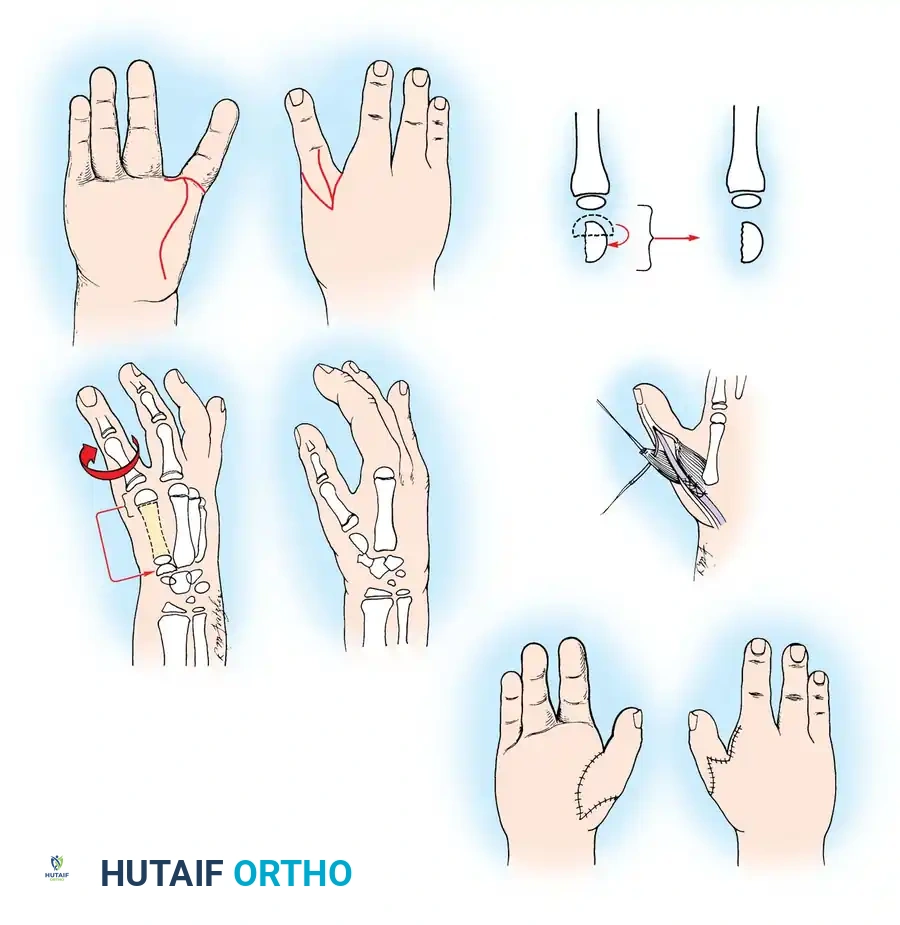

Fig. 76-2 Failure of formation (digital nubbins). The presence of functional wrist motion allows the limb to be used effectively as an assisting hand.

Hypoplasia of the more proximal musculature is a key clinical finding that helps differentiate true transverse deficiencies from amputations caused by congenital constriction band syndrome (amniotic band sequence). In the most common presentation—the upper forearm amputation—the forearm is usually no more than 7 cm long at birth and will reach a maximum length of approximately 10 cm by skeletal maturity.

In midcarpal amputations (the second most frequent level), the rudimentary digital remnants are almost always nonfunctional. However, because the radiocarpal joint is preserved, pronation and supination are usually possible, providing a highly functional assisting limb. Cognitive development and intelligence in these children are generally normal.

Surgical Warning: Prosthetic management for midcarpal amputations remains controversial. The long, below-elbow stump is exceptionally useful for stabilizing objects and bimanual function because it retains native sensibility. Sacrificing terminal sensibility for a cosmetic artificial hand must be carefully weighed against the functional loss.

Surgical Interventions in Transverse Deficiencies

Surgical indications for transverse deficiencies are exceedingly rare. Epps, Burkhalter, and McCollough reported that out of 1,077 children